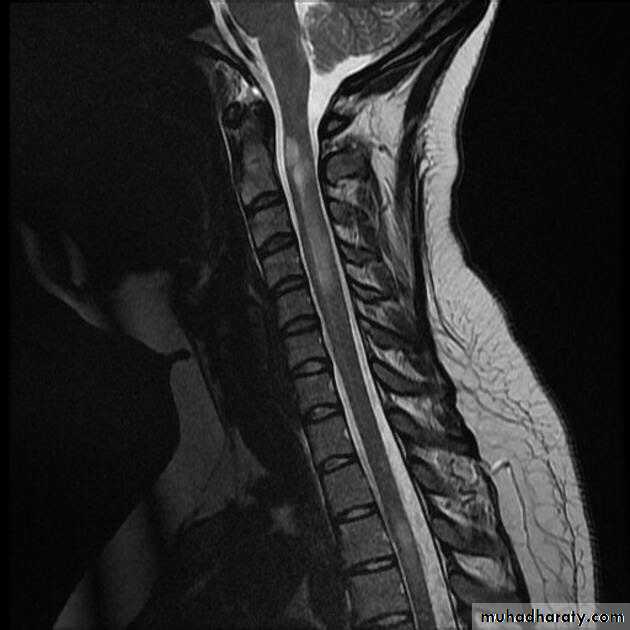

Neuromyelitis optica (NMO), or Devic’s syndrome, is an aggressive inflammatory disorder consisting most typically of attacks of acute ON and myelitisAttacks of ON can be bilateral (rare in MS) or unilateral

myelitis can be severe and transverse (rare in MS) and is typically longitudinally extensive, involving three or more contiguous vertebral segments